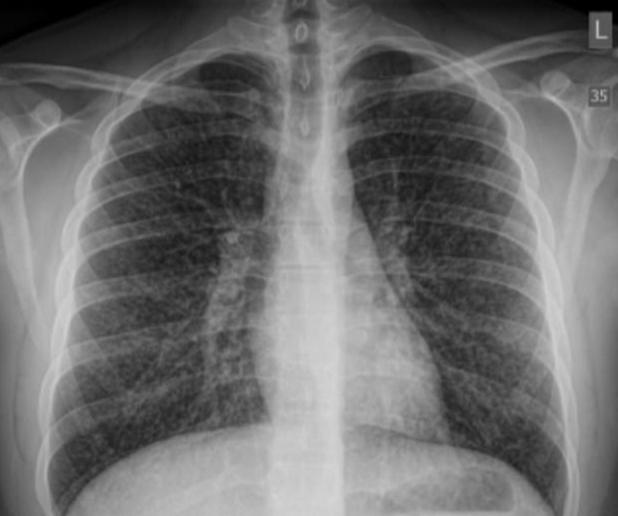

在为少年进行了一系列X光和CT扫描后 , 医生们得出了结论 , 他患上了闭塞性细支气管炎 , 也叫“爆米花肺” 。 这是一种严重的不可逆性肺部损伤 , 通常是由于吸入二乙酰引起的 。 尽管二乙酰可以安全食用 , 但吸入却是致命的 。 医生们认为 , 少年吸食的烟油中一定是加入了二乙酰或是类似的化学物质 。